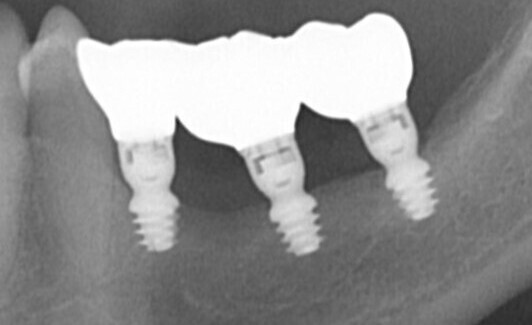

IMPLANTOLOGIE : LES BRIDGES FIXES PARTIELS